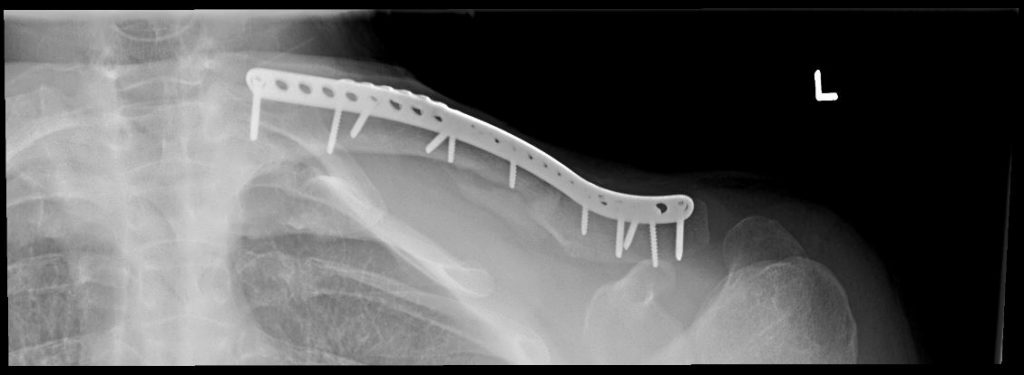

After getting back to New York I scheduled a visit with Dr. Daniel Dziadosz at HSS. Dr. Dziadosz confirmed my worst fears, my collar bone was displaced and broken in multiple places. Dr. Dziadosz explained the nature of the injury and the steps involved in surgery and my rehabilitation. He made me feel comfortable and confident. I knew I was in the right place.

The operation went well. I've got two plates and 11 screws. Six months later I feel great. I am swimming, biking and waiting for the next skiing season.